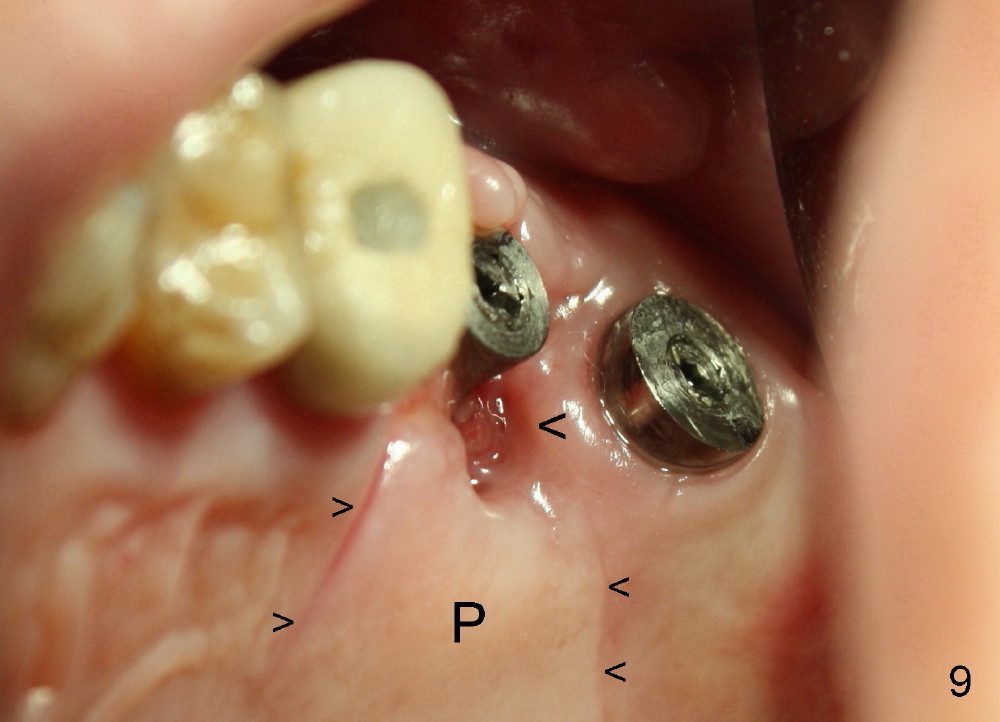

In spite of releasing buccal and palatal (P) flaps with suturing (Fig.8,9 small arrowheads), the palatal socket is exposed 2 weeks postop (big arrowhead and ). The mesiobuccal bone is also exposed (Fig.8 *). The patient reports bleeding and pain immediately postop. Both can be prevented if a large healing abutment is used (8 or 9 mm in diameter) or an immediate provisional is fabricated.